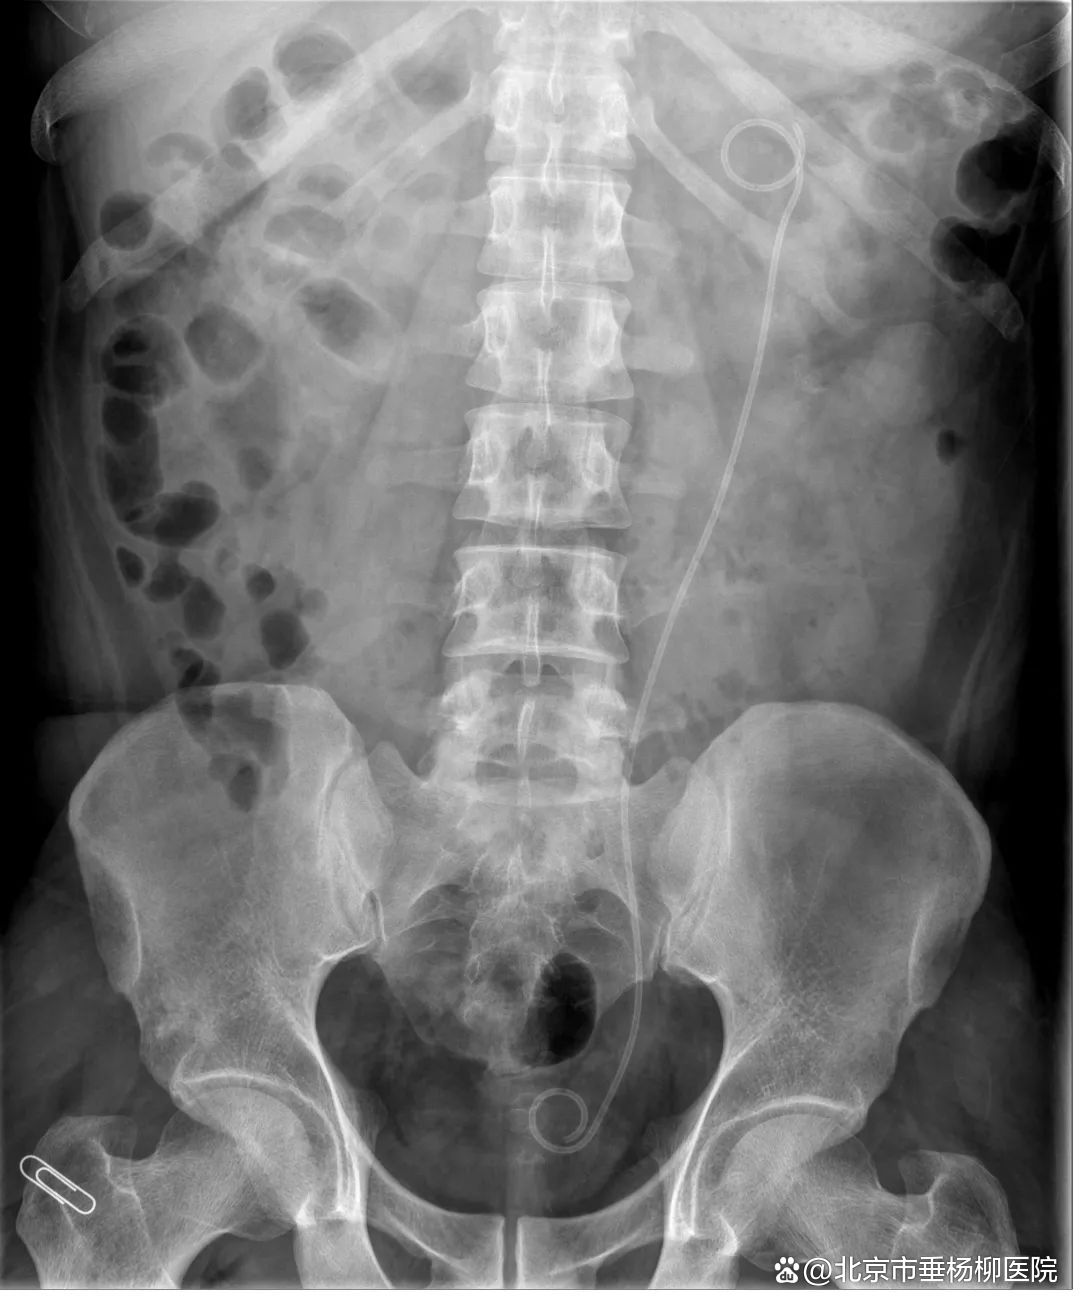

“好的,马上就来。”挂了电话,他立即赶到急诊外科。急诊科医生首先介绍了患者病情,患者是一位30岁的青年男性,主诉左腰部疼痛2小时,已完善腹盆部CT,但因为语言问题,其他信息沟通困难,目前诊断尚不确定。王凯歌仔细查看了患者的CT,发现左肾中下盏多发形态不规则高密度影,长径约4.5cm,考虑左肾巨大结石。

▲术前(箭头为结石)

1个月后,按照诊疗计划,泌尿外科团队再次成功完成了Ⅱ期左侧输尿管软镜钬激光碎石取石术。术后复查泌尿系平片提示左肾结石已全部粉碎。